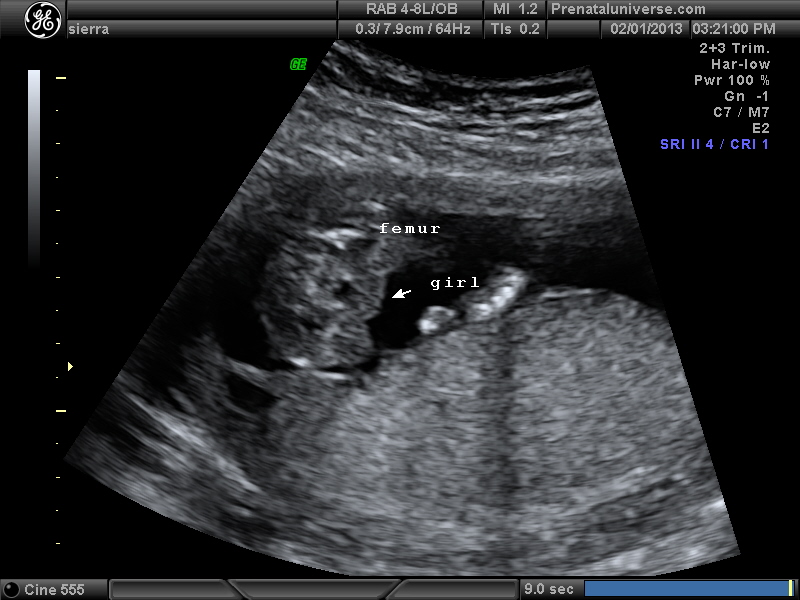

UPDATE!!!! Tech says girl. I was 16 w 1 day. Everyone agree? Nub shots were no help. Hoping this potty shot is more clear. In the video there were times it looked like there was something between legs but every still shot looks Girly I think:) Ty everyone :)

I'm curious about the area behind the black spot. I believe he said black spot is babys bladder. the area the arrow is pointing to looks girly but the area behind the black spot looks different??? thanks all